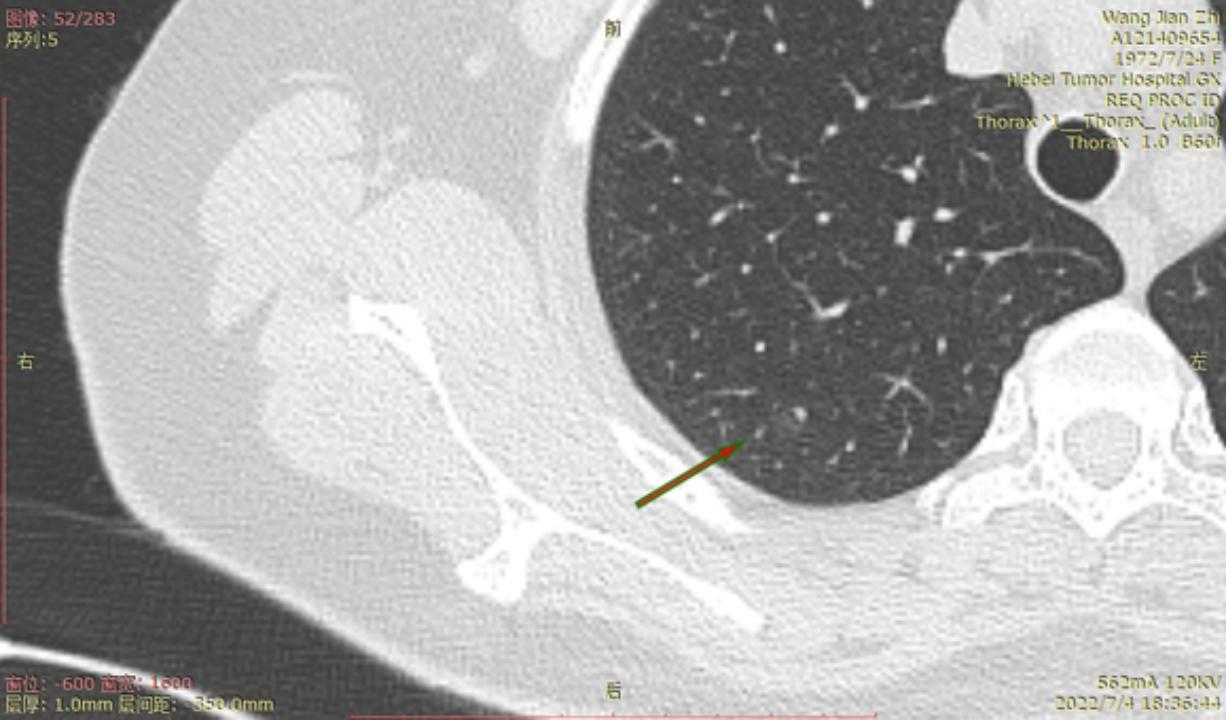

结4-5

右侧至少5枚以上的微浸润或原位腺癌,大的两枚结节微浸润,建议半年内把右侧5mm以上或者有危险的结节一网打尽。左侧结节还安全,安心随访